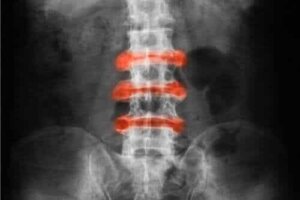

Wat is dit voor een ziekte? Spondyloartritis is inflammatoire artritis die voornamelijk in de gewrichten van de rug en het bekken voorkomt. Acute aandoeningen en stijfheid hebben de neiging om met fysieke activiteiten te verbeteren, en inactiviteit kan het erger maken.

- De ziekte van Bechterew. Dit is inflammatoire artritis die voornamelijk de wervelkolom aantast.

- Axiale spondyloartritis (AxSpA). Dit veroorzaakt ontsteking in de wervelkolom die zowel de ziekte van Bechterew, enteropathische artritis, reactieve artritis, artritis psoriatica als ongedifferentieerde spondyloartritis omvat.